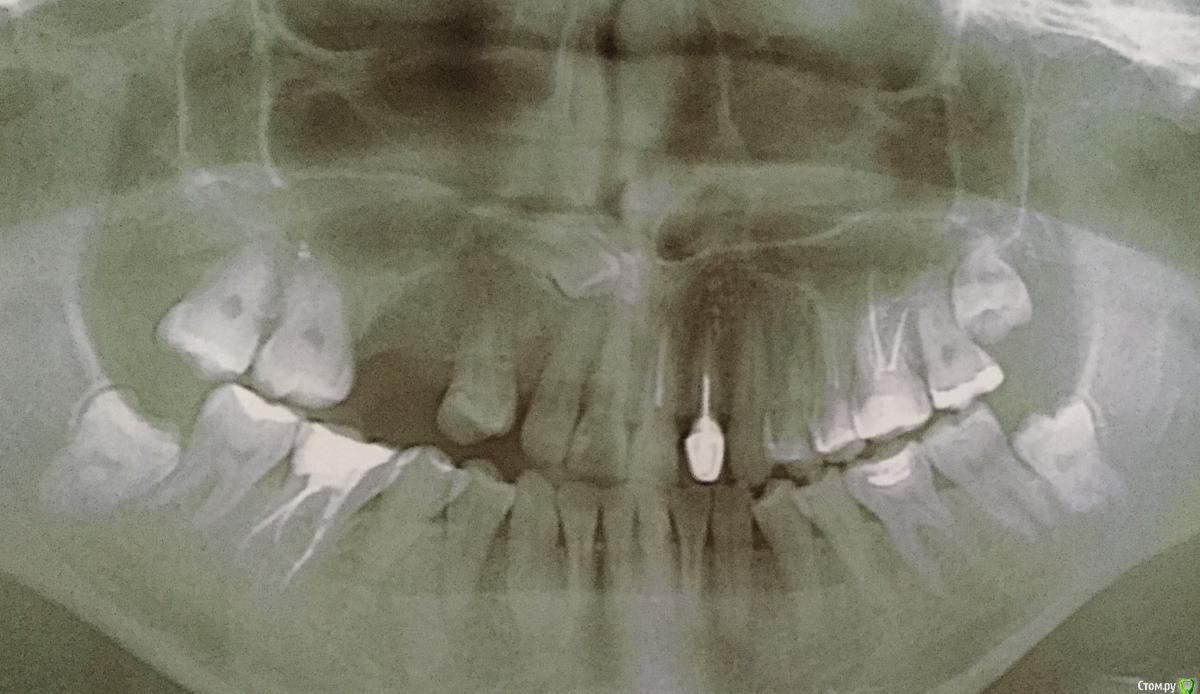

Innaiii Опубликовано 22 октября, 2018 Поделиться Опубликовано 22 октября, 2018 Здравствуйте!у меня неправильный прикус верхней челюсти одна сторона ниже другая выше, также ретированный клык он лежит высоко возле носа ещё и поперёк!Подскажите что мне сделать с зубами думала одеть брекеты, но сомневаюсь что эту кривизну уже не исправить, зубы по длине разные!Или после брикетов нужно будет визиры ставить чтоб длину выпрямить?Может есть ещё какие то варианты? Ссылка на комментарий